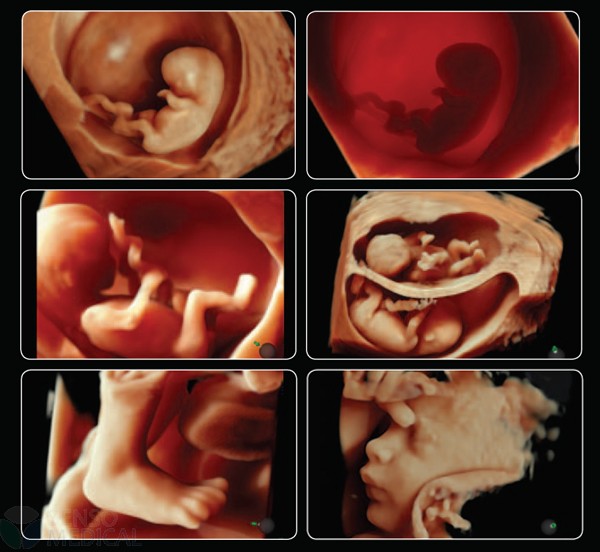

Ultrasonograf GE Voluson E6 wersja oprogramowania BT13 (UISApp 13.0.6.254) 4D HDLive –

rekondycjonowany 2019

Innowacyjna sonda endowaginalna 4D o wysokiej rozdzielczości pomaga odkryć najdrobniejsze szczegóły i pomaga zwiększyć pewność diagnostyczną.

System Voluson E6 to unikalne rozwiązanie w zakresie diagnostyki chorób kobiecych oferujące wysoką jakość obrazowania w trybach 2D i 3D/4D oraz uproszczone procedury usprawniające przepływ pracy i zapewniające najwyższą jakość badań. Więcej szczegółów, mniej wysiłku!